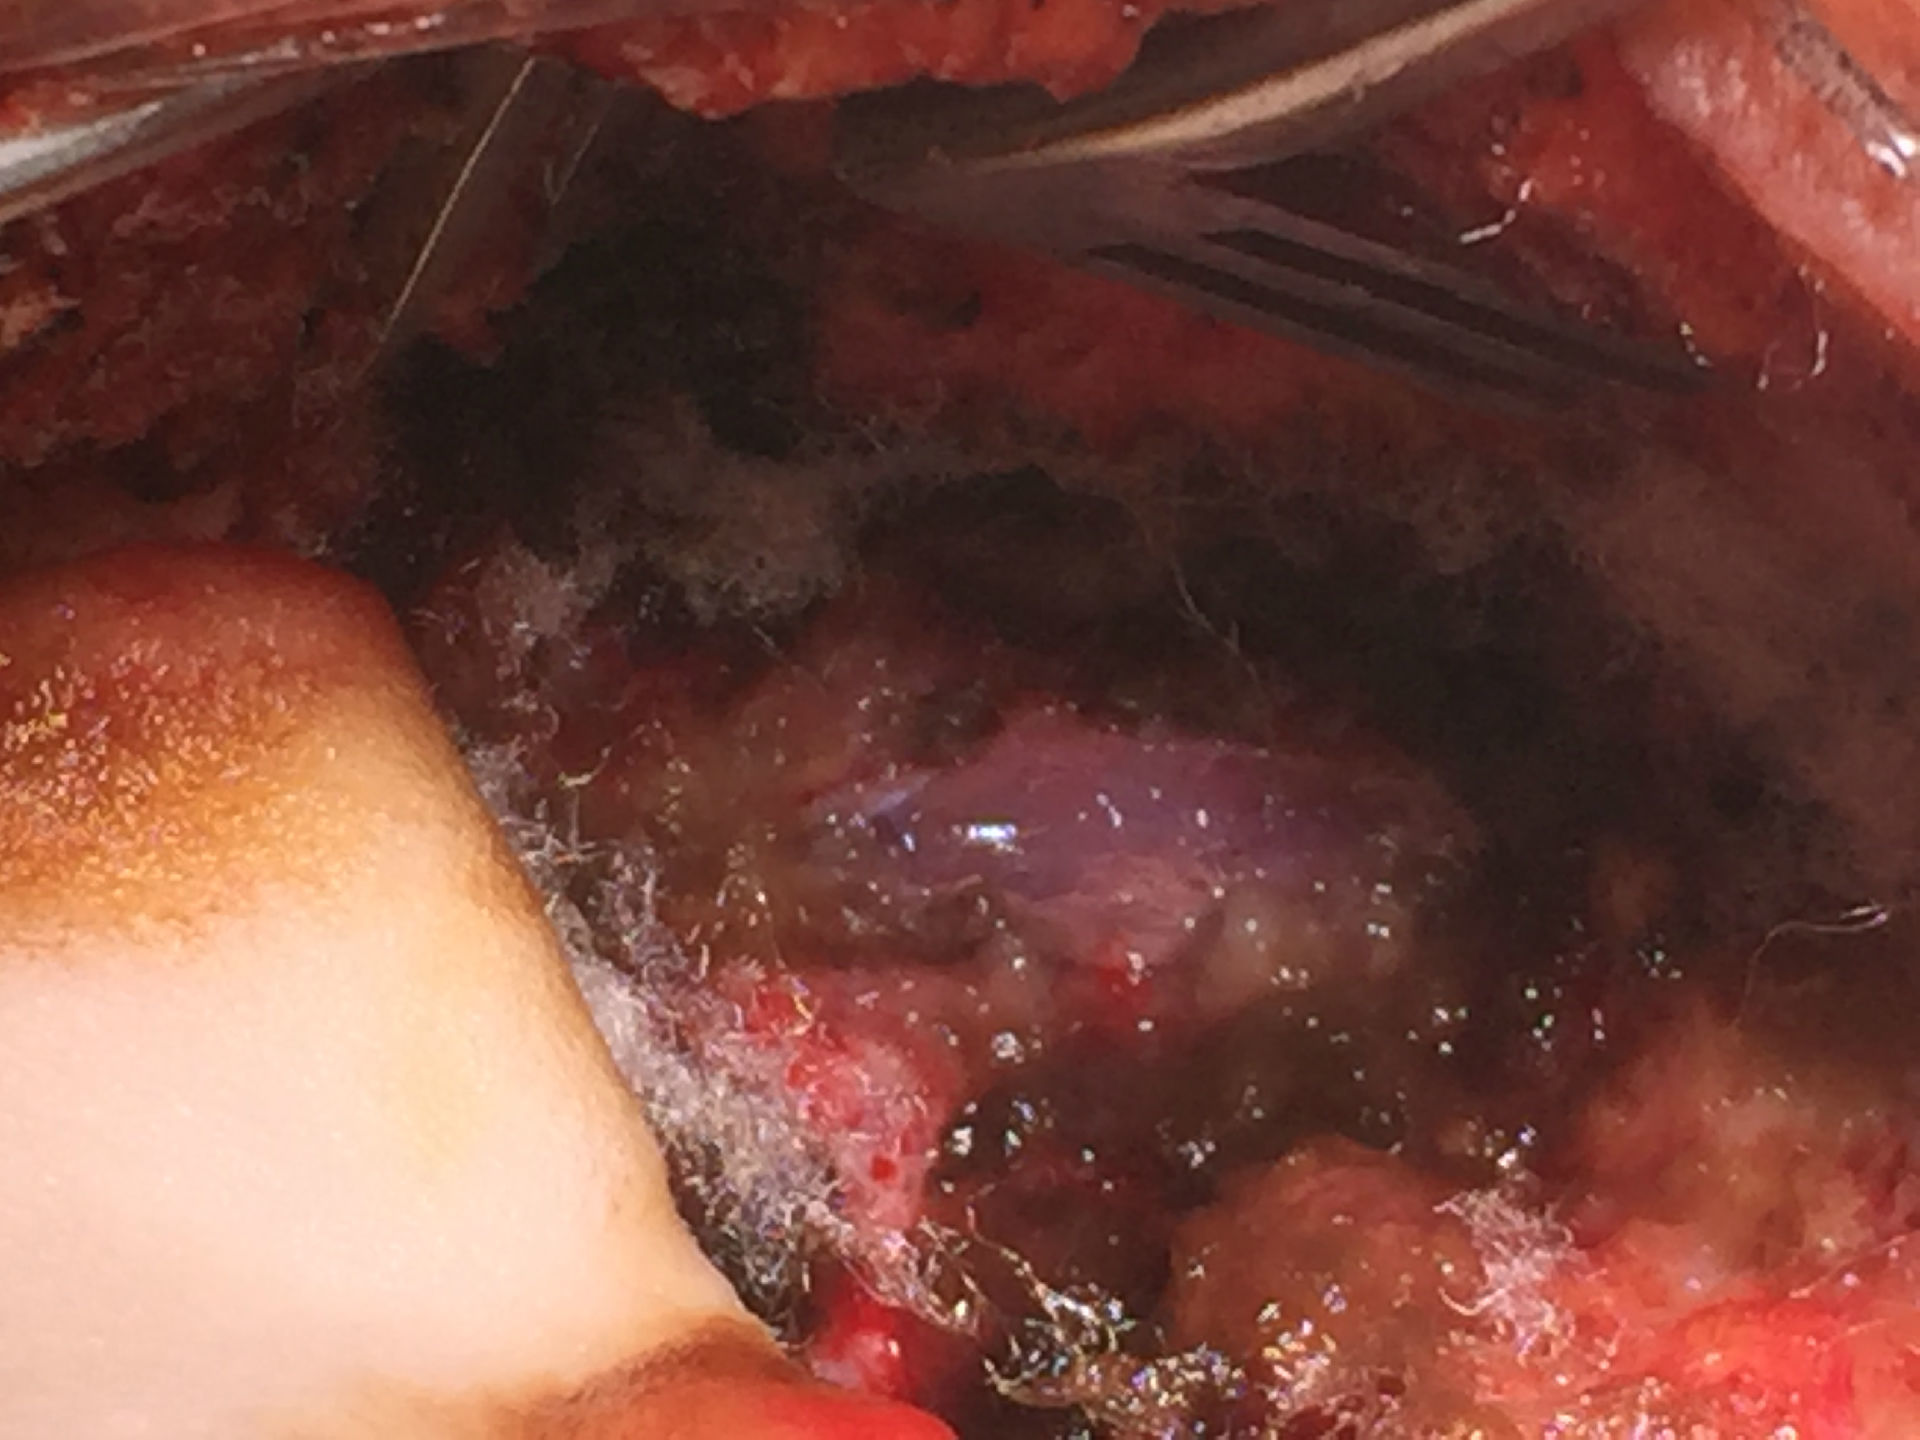

小脑扁桃体下疝畸形单纯骨性减压

图片尺寸2667x2000